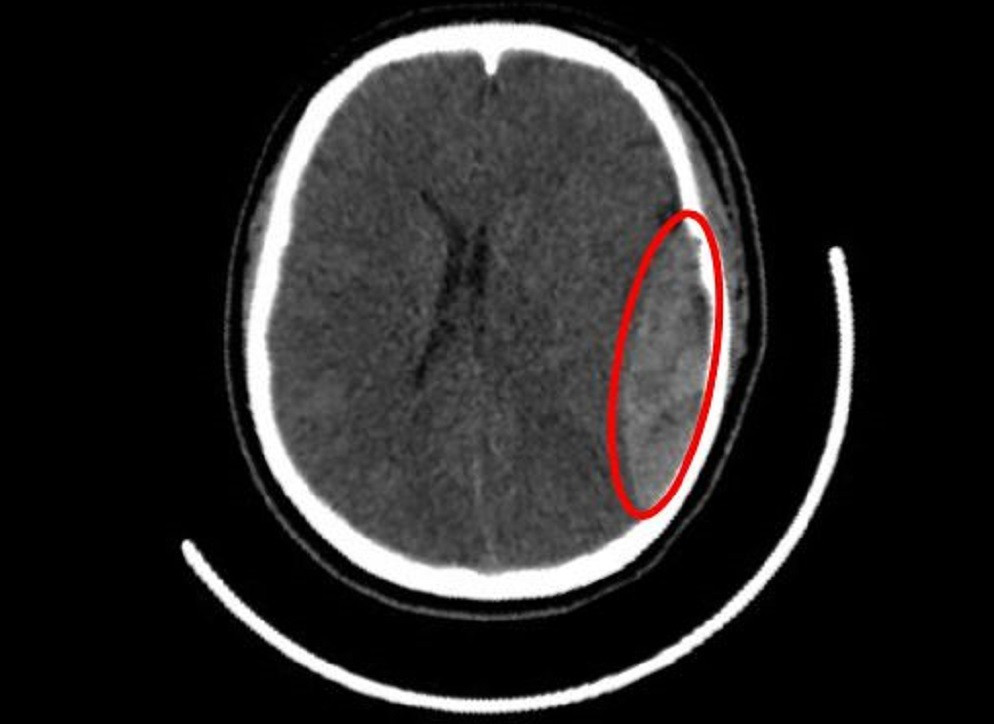

Tại khoa Cấp cứu, các bác sĩ ghi nhận bệnh nhân bị yếu nửa người bên phải, tri giác giảm còn khoảng 9–10 điểm Glasgow. Kết quả kiểm tra hình ảnh cho thấy, một khối máu tụ ngoài màng cứng ở bán cầu não trái lan xuống vùng thái dương, kèm theo nứt xương hộp sọ thái dương. Khối máu tụ có dấu hiệu tăng thêm, nghi do đứt động mạch màng não giữa – một vị trí chảy máu lớn và nguy hiểm.